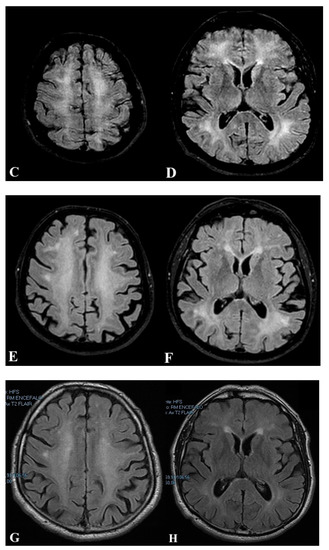

2.1. First Case

2.2. Second Case